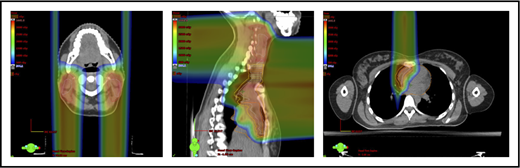

Proton therapy can significantly reduce the radiation dose to the breasts by specifically using fields that enter posteriorly and stop short of exiting through the breast. Alternatively, if protons cannot be used, other methods of displacing the breast can be used instead, such as using an inclined board or physically moving the breast out the beam path. Figure 3A shows how using proton therapy can spare the breast in a case with axillary involvement.

Axillary involvement at presentation. (A) Axial, coronal, and sagittal views of a proton plan (left) and an IMRT plan (right) for a patient presenting with axillary involvement. Use of proton therapy in this case spares the left breast. (B) Regardless of which treatment modality is chosen, IMRT (left panel) and proton (right panel), limiting the volume exposed to radiation should include attention to avoiding a low-dose bath. (C) Limiting lung dose. If avoiding the lung is the primary objective in a given patient, especially if the patient has received pulmonary toxic chemotherapy (eg, any combination of bleomycin, busulfan, gemcitabine, brentuximab, etc.), proton therapy may better spare the lungs by reducing the low-dose bath seen with photons.

When hilar disease needs to be covered, the dose to the breasts can increase, and avoiding the breasts becomes difficult with either modality (proton or photon). The choice of treatment modality for such cases must consider the doses received by other critical structures, such as the heart and lungs, especially in previously and heavily treated patients. However, in considering how to best limit the volumes exposed to radiation, avoiding “low-dose baths” is equally important (ie, irradiation of large volumes with low doses), regardless of which modality is used (Figure 3B).

Consideration of lung dose

With the advent of CT-based planning for mediastinal lymphoma, the dose to the lungs can now be correlated with the risk for pneumonitis. Restrictions on lung dose are encouraged to be V5 < 55%, mean lung dose < 13.5 Gy, and V30 < 20%. These values are more attainable with the use of DIBH.38 Although a mean lung dose of 13.5 Gy has been associated with a lower risk for pneumonitis, it is advisable to aim for a lower dose, which is quite often attainable when strict constraints are used. For example, when IMRT is used, it is important to limit the beams to some variation of anteroposterior beams, avoiding lateral beams. If avoiding the lung is the primary objective for a given patient, especially if that patient has received pulmonary-toxic chemotherapy (eg, bleomycin, busulfan, gemcitabine, brentuximab), proton therapy may better spare the lungs by reducing the low-dose bath seen with photons (Figure 3C).